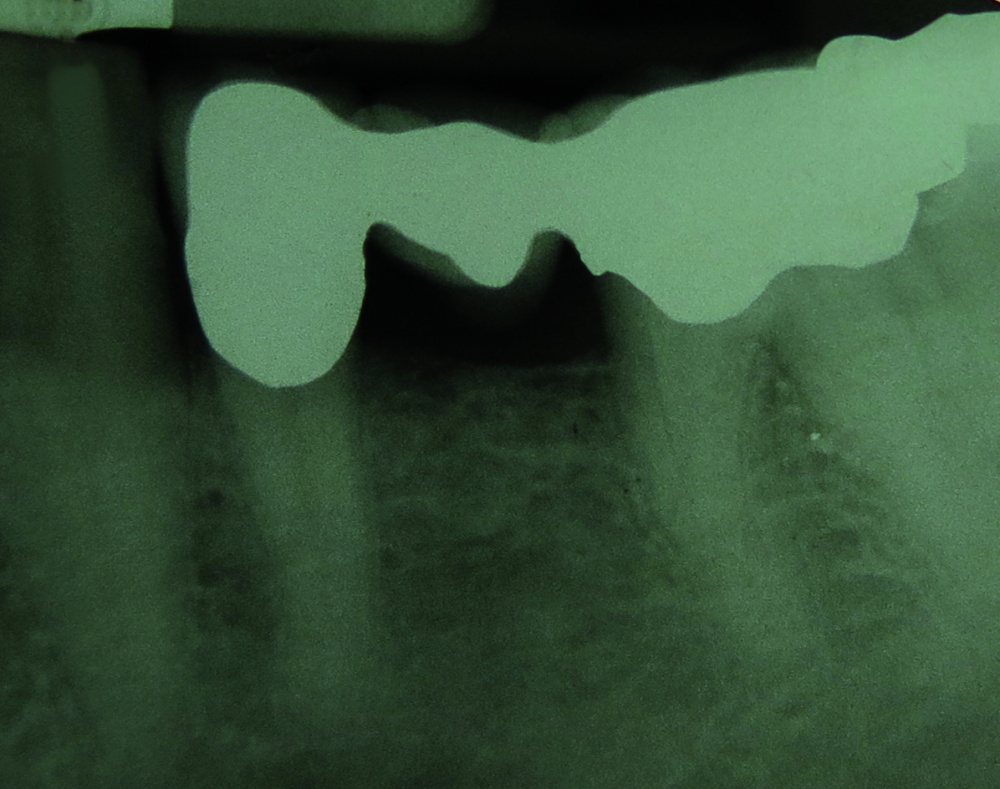

Auf einer angefertigten Panoramaschichtaufnahme konnten keine pathologischen Befunde festgestellt werden. Eine von der Region 36 angefertigte intraorale Zahnfilmaufnahme (Abbildung 2) zeigte – soweit dies bei metallischen Restaurationen beurteilbar ist – ebenfalls keine Anzeichen für eine Sekundärkaries am Brückenpfeiler Zahn 36 oder Hinweise auf apikale Veränderungen.

Für die Behandlung von Myopathien hat sich die sogenannte Äquilibrierungsschiene (Synonym: Relaxierungsschiene, Stabilisierungsschiene) bewährt [1, 13, 17, 18]. Diese Schiene ist gekennzeichnet durch eine gleichmäßige Abstützung der Seitenzähne in der Statik und eine Front-Eckzahnführung bei dynamischen Unterkieferbewegungen nach anterior oder nach lateral (Abbildung 2).